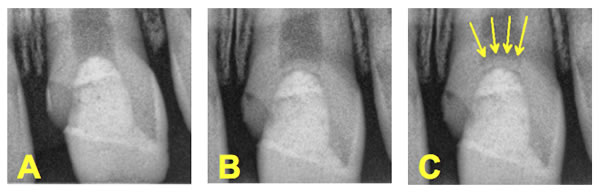

Figure 9. A close up of the calcific bridge formation. Immediately after Pulpotomy completed (A) and 4 month recall (B and C).

In the case of immature teeth, an attempt can be made to perform a full pulpotomy (removal of all pulp tissue within the chamber) (Figures 8 and 9) or even a deep pulpotomy (removal of pulp tissue beneath the cemento-enamel junction) in effort to reach healthy bleeding pulp tissue, at which the capping procedure can then be performed.